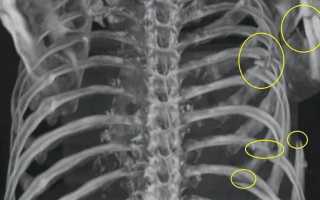

Для более точной диагностики используются визуализирующие методы. Рентгенография является стандартным методом для выявления переломов ребер. На рентгеновских снимках можно увидеть линии перелома и оценить состояние окружающих тканей. Однако, в случае сложных травм или подозрений на наличие повреждений внутренних органов, может потребоваться более детальное исследование, такое как компьютерная томография (КТ). Этот метод позволяет получить более четкие изображения и выявить даже мелкие переломы, а также оценить состояние легких и других органов грудной клетки.